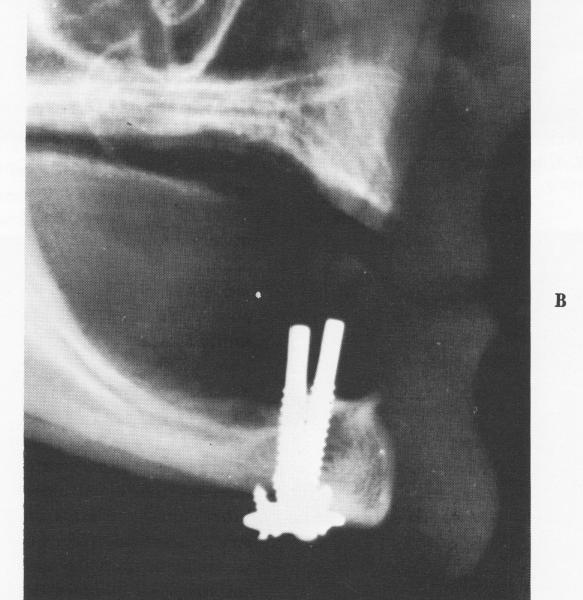

Fig. 5-61. When the transfixation screws have been inserted, smaller locking screws are used to stabilize them. A, Anteroposterior view of the screws in place. The patient also had prior arthroplastic surgery on the left temporomandibular joint. B, A lateral plate showing the implants. Note that they are anterior to the mental foramina. (Courtesy R. W. Christensen.)

1 Small locking screw stabilizes endosseous implant transfixation screw

2 Lateral plate shows endosseous implant transfixation screws in place